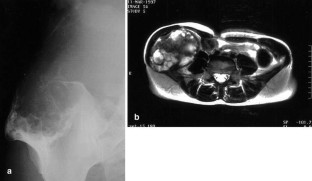

Spontaneous malignant transformation of conventional giant cell tumor (GCT) of bone is exceedingly rare. We report on a case of GCT of the iliac crest in a 35-year-old woman with malignant change into a high-grade osteosarcoma 10 years after the first appearance of GCT on a radiograph. Since the patient refused therapy for personal reasons the tumor remained untreated until sarcomatous transformation occurred. Image cytometry showed DNA aneuploidy and a suspiciously high 2c deviation index (2cDI) in the primary bone lesion. A thorough review of the world literature revealed only seven fully documented cases of secondary malignant GCT which matched the definition of a “sarcomatous growth that occurs at the site of a previously documented benign giant cell tumor” and not treated by radiotherapy. These cases as well as the current one suggest that a spontaneous secondary malignant GCT presents as a frankly sarcomatous tumor in the form of an osteosarcoma or malignant fibrous histiocytoma. It usually appears at sites of typical GCTs—often without any recurrent intermediate state—and is diagnosed 3 or more years after the primary bone lesion. The prognosis is poor.

Fig. 1

Fig. 2